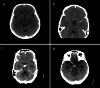

Figures